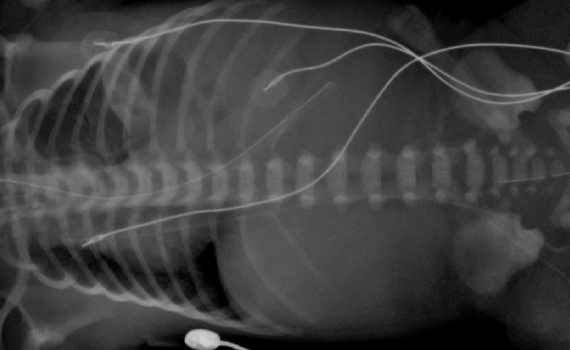

Manejo del lactante con estridor